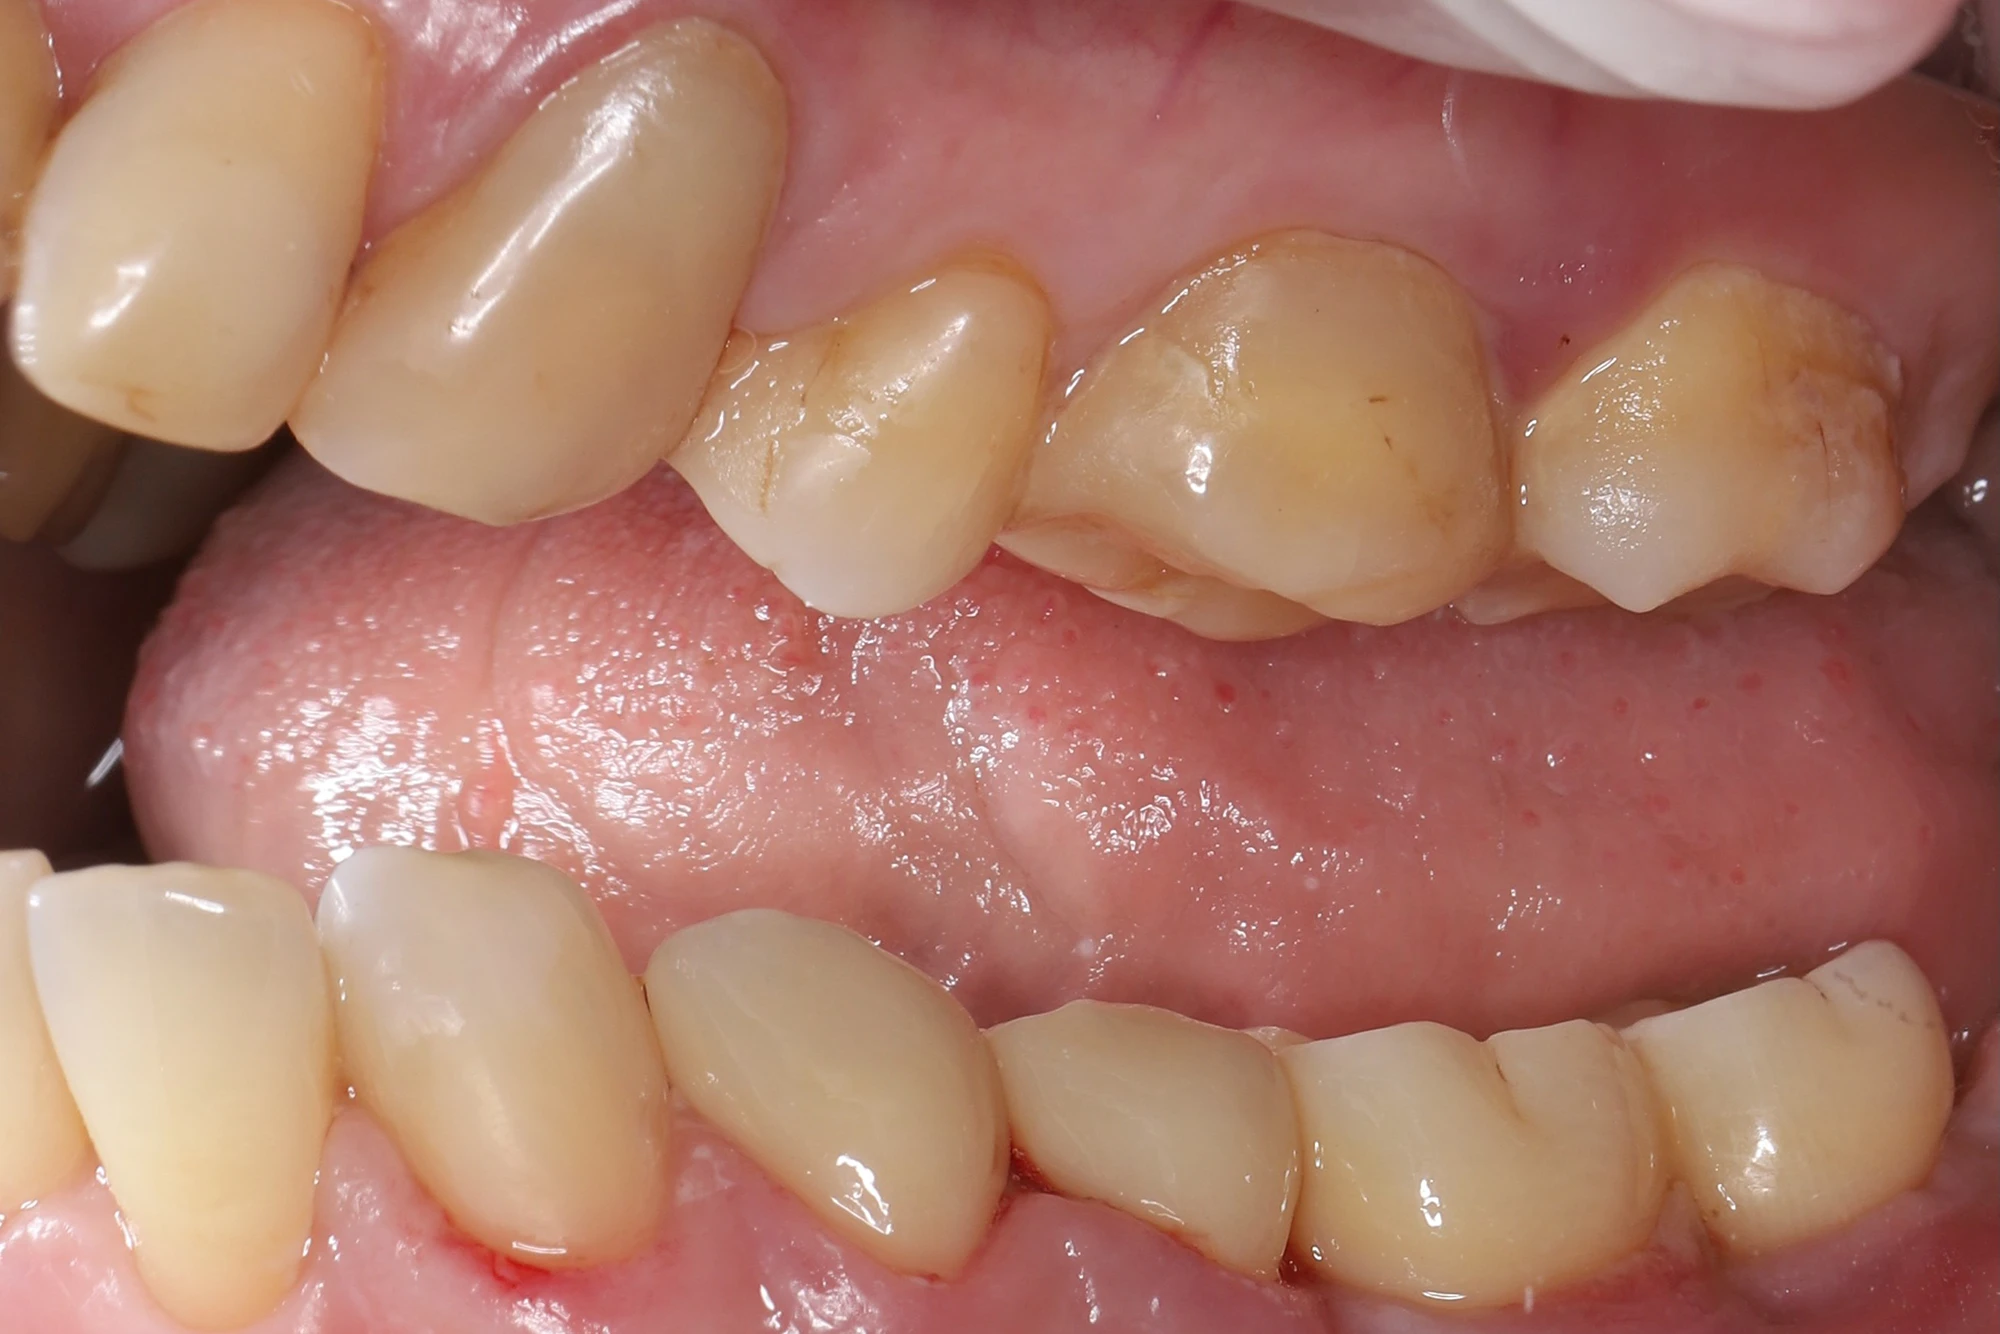

Был выполнен КТ-снимок и выявлены хронический периодонтит и кариес корня 37 зуба под опорной металлокерамической коронкой. 36-й зуб был утрачен давно, 35-й, также опорный, ранее эндодонтически пролечен — без особенностей. 34-й зуб — только с пломбой после лечения корневого канала.

Проведено атравматичное удаление 37 зуба. Через 3 месяца после оценки костной ткани было выполнено интраоральное сканирование, напечатан хирургический шаблон и установлены два имплантата Ritter в области 36 и 37 зубов. Наложены швы, даны рекомендации по уходу.

3 месяца была выполнена контрольная рентгенография: костный уровень сохранен, признаков воспаления нет, имплантаты остеоинтегрированы. Проведено раскрытие имплантатов и установлены индивидуализированные формирователи десны.

Во время визита пациентки в клинику были проверены посадка ортопедических реставраций, их краевое прилегание, окклюзионные контакты, симметрия и эстетическая составляющая. Пролечен контактный и пришеечный кариес на 33 зубе. Коронки на имплантатах зафиксированы винтовым способом, на своих зубах — на стеклоиономерный цемент.

- Восстановлена жевательная функция в левом сегменте нижней челюсти.

- Достигнута хорошая эстетика: циркониевые реставрации на зубах и имплантатах гармонично сочетаются по цвету и форме.